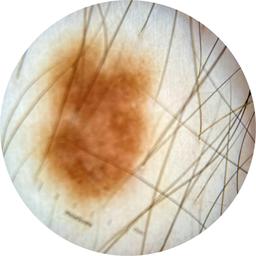

ISIC_8121870

anatom_site_1 Trunk

anatom_site_2 Posterior trunk

anatom_site_general posterior torso

diagnosis_1 Benign

image_type dermoscopic